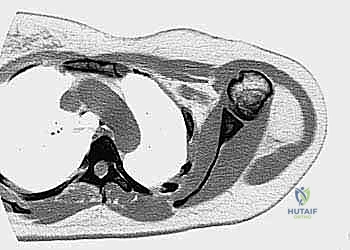

- الأشعة المقطعية (CT Scan): ضرورية لتقييم القشرة العظمية والتكلسات داخل الورم، وللبحث عن أي انتشار في الرئتين.

يعتمد الأستاذ الدكتور محمد هطيف على دراسة هذه الصور الإشعاعية شخصياً قبل تحديد مسار إبرة الخزعة، لضمان عدم تلويث الحجرات العضلية السليمة (Compartments).

لضمان أخذ العينة من الجزء الأكثر تمثيلاً للورم وتجنب المناطق الميتة (Necrotic areas)، يستخدم الدكتور هطيف جهاز الأشعة المقطعية أو جهاز القوس المفلور (C-arm) لتوجيه الإبرة في الوقت الفعلي.

الحالة الأولى: إنقاذ ركبة رياضي شاب

شاب يبلغ من العمر 19 عاماً عانى من ألم مستمر في الركبة وتورم لم يستجب للمسكنات. بعد الفحص السريري الدقيق وإجراء الرنين المغناطيسي، اشتبه الأستاذ الدكتور محمد هطيف بوجود ورم. تم إجراء خزعة إبرة أساسية دقيقة جداً. أظهرت النتائج وجود "ساركوما عظمية" في مراحلها الأولى. بفضل الخزعة الدقيقة التي لم تلوث الأنسجة المحيطة، تمكن الدكتور هطيف لاحقاً من استئصال الورم بالكامل وتركيب مفصل صناعي خاص بالأورام، مما أنقذ ساق الشاب من البتر ومكنه من العودة للمشي بشكل طبيعي.